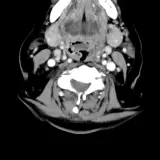

Casos totalmente interativos com as ferramentas que você espera em um PACS — rolagem, ajuste de janela, zoom, movimentação, medidas, ROIs e modo de tela cheia.

Anotações detalhadas destacam os achados principais diretamente nos casos. Clique nos achados vinculados nas descrições dos casos para ir ao local exato no exame.